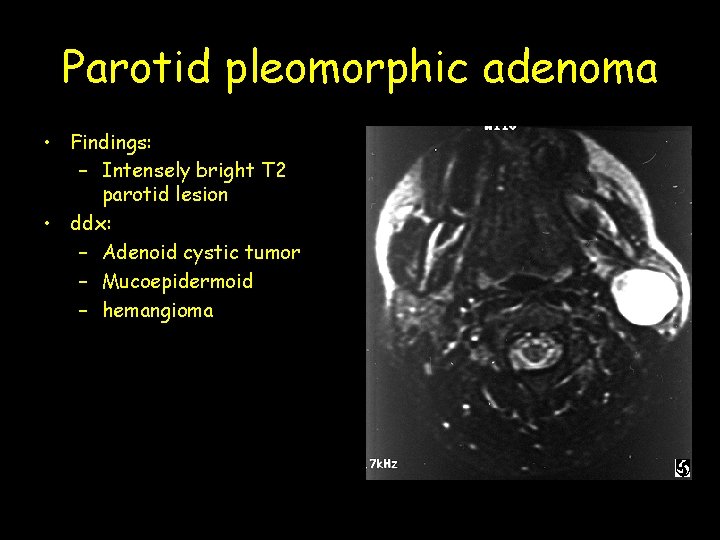

Parotid pleomorphic adenoma • Findings: – Intensely bright T 2 parotid lesion • ddx: – Adenoid cystic tumor – Mucoepidermoid – hemangioma